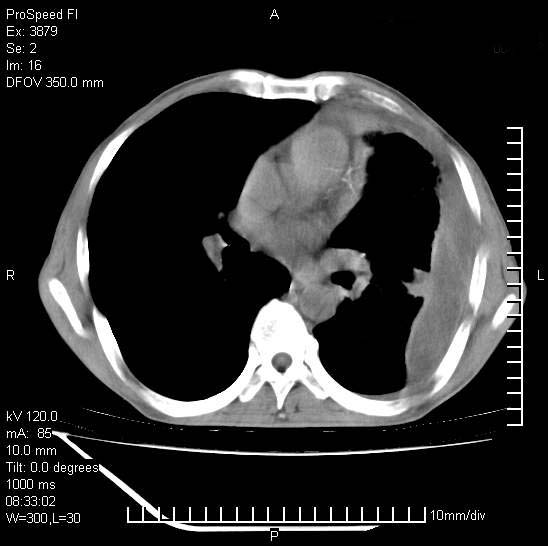

以下是引用37度在2008-6-6 11:20:00的发言:[br]1.包裹性积液,多考虑结核性;[br]2.穿刺术后改变。

以下是引用312nanyang在2008-6-6 15:12:00的发言:[br]基本支持楼主意见[br]疑问?左下肺支气管旁的软组织(16层)密度怎么解释?淋巴结还是斜裂胸膜增厚所致?能否增强进一步检查